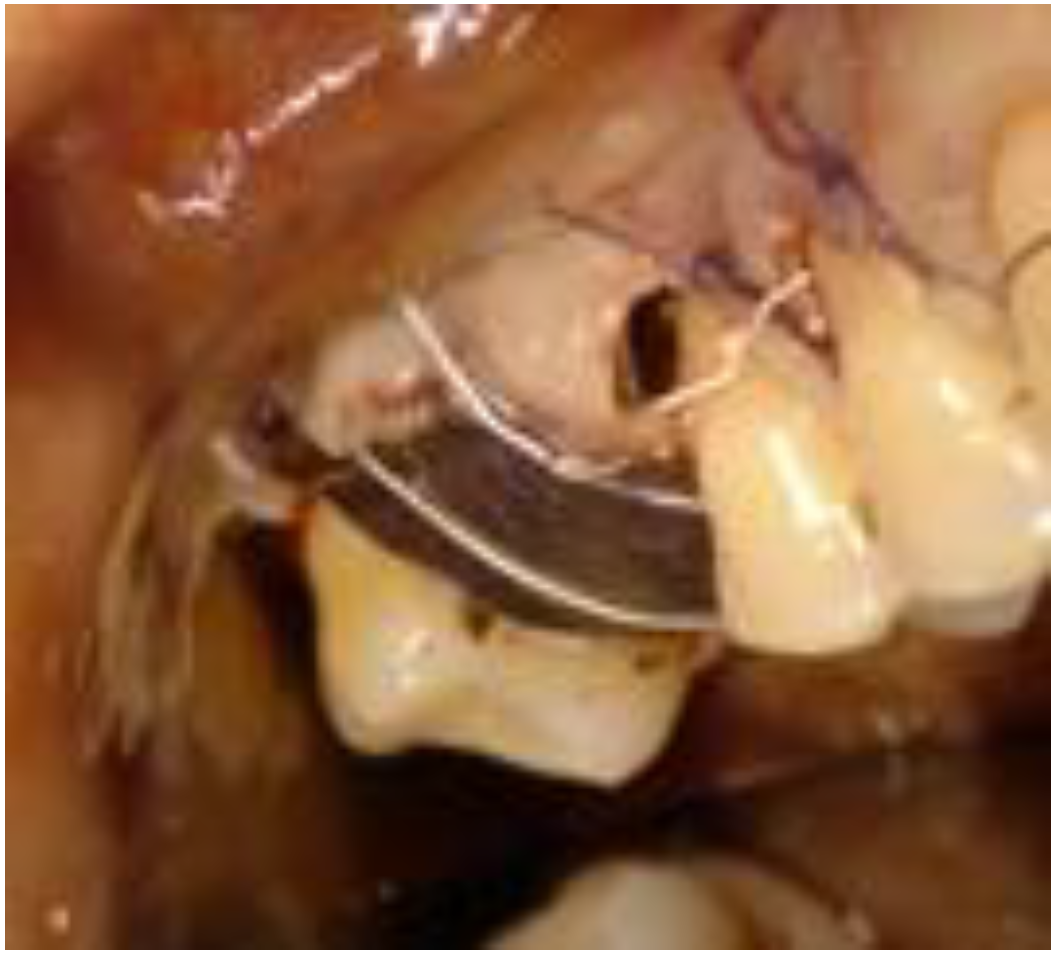

2.1. Clinical and Surgical Procedures